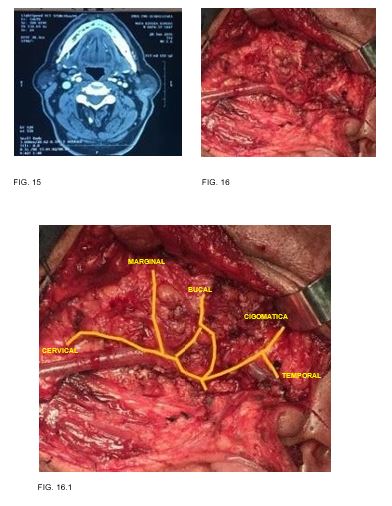

Caso 8: masculino de 59 años de edad, antecedente de diabetes mellitus y tabaquismo con tumor parotídeo izquierdo de 3cm en su eje mayor resultando en tumor de Warthin (FIG. 15-16)

Caso 9: masculino de 64 años de edad, antecedente de diabetes mellitus 2, tabaquismo y etilismo con tumor parotídeo izquierdo de 4cm en su eje mayor resultando en tumor de warthin.